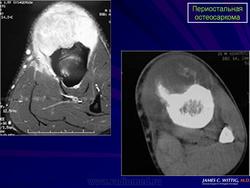

Рентгенологическая картина выявляет очаг поражения на поверхности кости. Очаговые фокусы кальциноза, формирование спикул, нечеткая граница опухолевого узла, мягкотканный компонент, отсутствие поражения медуллярного отдела кости, все названные рентгенологические признаки характерны для периостальной остеосаркомы. Для выявления характера поражения костномозгового канала проводится дополнительное исследование с применением КТ и МТР.

Макроскопическая картина при периостальной остеосаркоме складывается из фокусов дольчатой, преимущественно хрящевидной, белесоватой опухолевой ткани на поверхности кортикальной пластинки кости без внедрения в костномозговой канал.

Микроскопическая картина при периостальной остеосаркоме имеет признаки хондробластического варианта остеосаркомы, но не обладает специфичностью. Характерно дольчатое строение, хондроидная дифференцировка клеток, умеренная степень атипии ядер опухолевых клеток.

Дифференциальная диагностика периостальной остеосаркомы достаточно сложна и включает остеохондрому, паростальную остеосаркому, классическую остеосаркому, поверхностную низкодифференцированную остеосаркому.